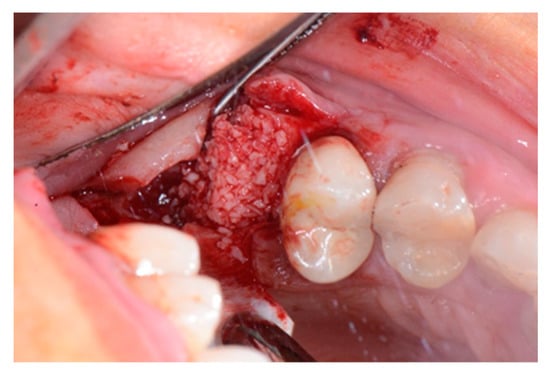

We used only surgical discarded material for the present study and the subject gave her informed consent before her participation. Seven days before the tooth extraction, the patient started prophylactic antibiotic therapy with amoxicillin/clavulanic acid (Augmentin, GlaxoSmithKline, Verona, Italy) and continued it for seven days after surgery 1 g/every 12 h, in addition to mouthwashes (chlorhexidine 0.2%) starting a week before surgery and continuing until healing occurred. Figure 2 shows the clinical situation after the crown removal. Once the extraction of tooth 26 (Figure 3) was carried out, the preservation of the alveolus was performed using a commercial enzymatically-deantigenated equine bone (Osteoxenon bone granules, Bioteck S.p.A, Vicenza, Italy) (Figure 4) and a commercial double layer of equine pericardium membrane (Heart pericardium membrane, Bioteck S.p.A., Vicenza, Italy) was used to cover and protect the site (Figure 5).

Figure 4.

Alveolar socket filled with the graft material.